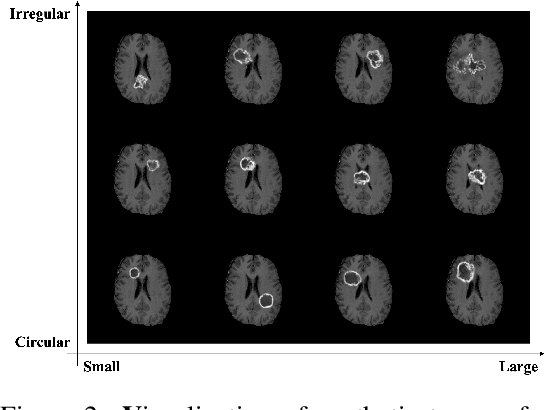

We introduce RadiomicsFill, a synthetic tumor generator conditioned on radiomics features, enabling detailed control and individual manipulation of tumor subregions. This conditioning leverages conventional high-dimensional features of the tumor (i.e., radiomics features) and thus is biologically well-grounded. Our model combines generative adversarial networks, radiomics-feature conditioning, and multi-task learning. Through experiments with glioma patients, RadiomicsFill demonstrated its capability to generate diverse, realistic tumors and its fine-tuning ability for specific radiomics features like 'Pixel Surface' and 'Shape Sphericity'. The ability of RadiomicsFill to generate an unlimited number of realistic synthetic tumors offers notable prospects for both advancing medical imaging research and potential clinical applications.